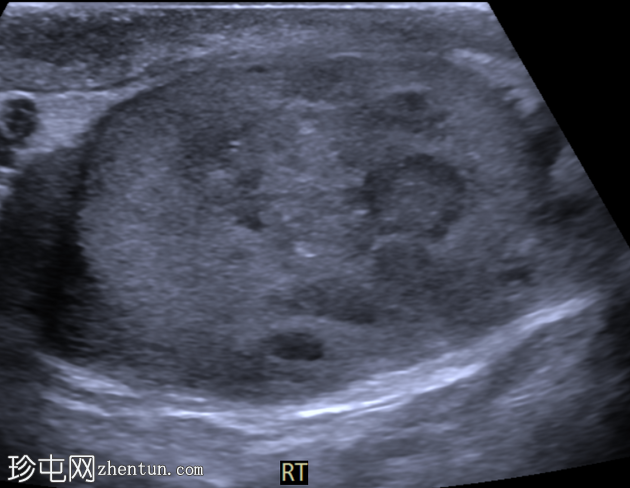

睾丸混合性生殖细胞瘤

右侧睾丸肿块,伴间歇性疼痛4个月。

年龄:30岁

性别:男

超声检查

横切面

右侧睾丸内可见一大小约3.0 x 5.0 cm的异质性分叶状低回声肿块。肿块内未见囊性区域或钙化。彩色多普勒超声检查显示肿块内血流丰富。左侧睾丸正常。